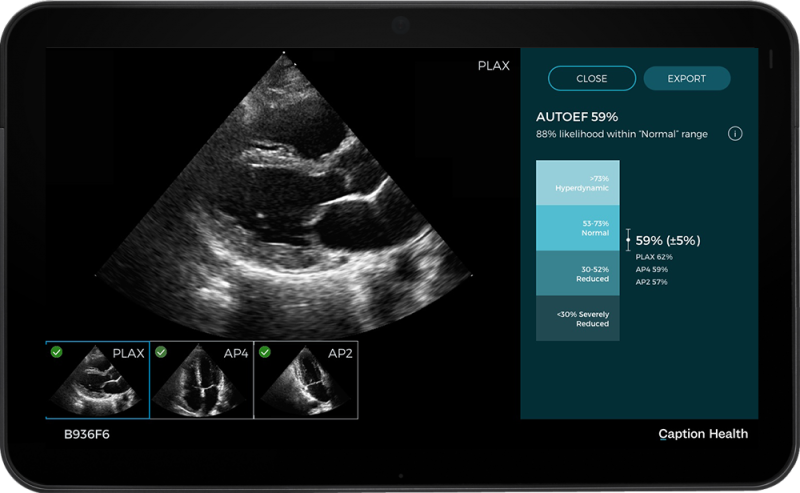

May 15, 2023 — GE HealthCare is presenting three new global innovations – Intelligent Radiation Therapy (iRT), Auto ...